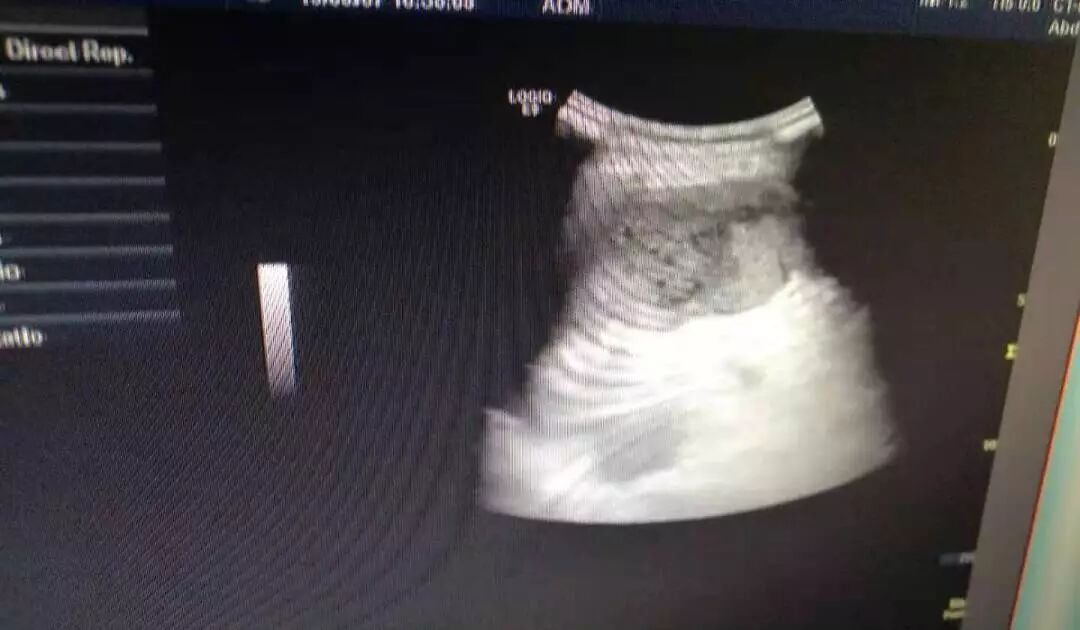

发现左上腹疼痛时,首选超声,CT检查。超声检查简便,时间短,能及时发现脾脏内病变,脾梗死超声表现呈棱形病灶,回声减低,当缺血坏死区扩大时,内可见不规则无回声区,超声彩色多普勒显示病灶区内无血流灌注。此患者经超声确诊过后,及时转上级医院做干预治疗,目前病情稳定。